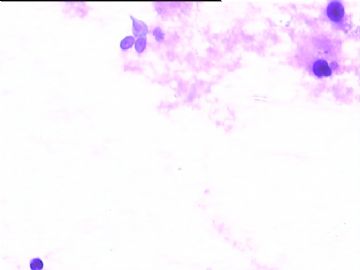

78y,男,胸水。 大家看看那些小于淋巴细胞的东东。

孢子?

图6感觉象是污染的孢子之类的东西。好好回忆一下,制片过程?容器?有没有污染的 可能?

但,最后一图的组织细胞内吞噬现象,怎么解释。

离体的细胞在一定的时间内还是活细胞,所以我推测吞噬细胞可能还是有一定的吞噬功能的。不过,确实也不能就排除了在活体内的微生物感染的可能。结合临床应该能够得到一定程度的澄清。